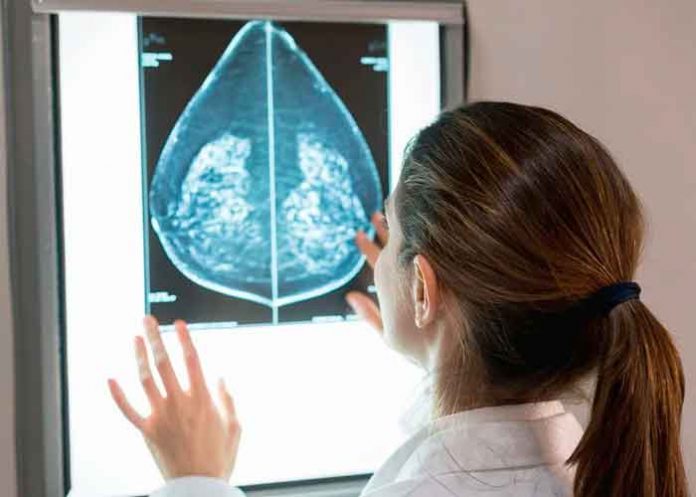

El equipo del Hospital Vall d’Hebron realizó diferentes experimentos in vitro e in vivo para conocer de qué manera Omomyc, desarrollado en el Vall d’Hebron, impactaba en las metástasis del cáncer de mama.

Los experimentos se hicieron tanto en modelos in vitro, para probar la eficacia en todos los tipos de tumores, como en modelos de ratón; centrados en el cáncer de mama triple negativo, una enfermedad que actualmente requiere mejores terapias.